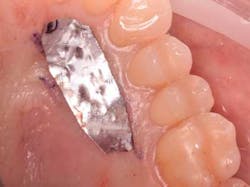

The following will now describe the free gingival autograft surgery that was used to augment the zone of keratinized tissue prior to orthodontic therapy. Three carpules of 3% Septocaine (Septodont, 1.7 ml carpule) was used as a local anesthetic for both infiltration of the donor palate area and inferior alveolar/mental nerve block of the recipient site. Injecting local anesthetic in the mucosa of the recipient site helps to identify the MGJ (mucogingival junction). A submarginal, split-thickness incision with a 15 blade was used to prepare the recipient site. Using aluminum foil to measure the amount of graft needed (figure 3), a full-thickness, free gingival graft was harvested from the upper right palate in the area of Nos. 3-6. Careful attention is paid not to harvest the site too anteriorly to avoid ruggae as well as limit increased post-operative pain.